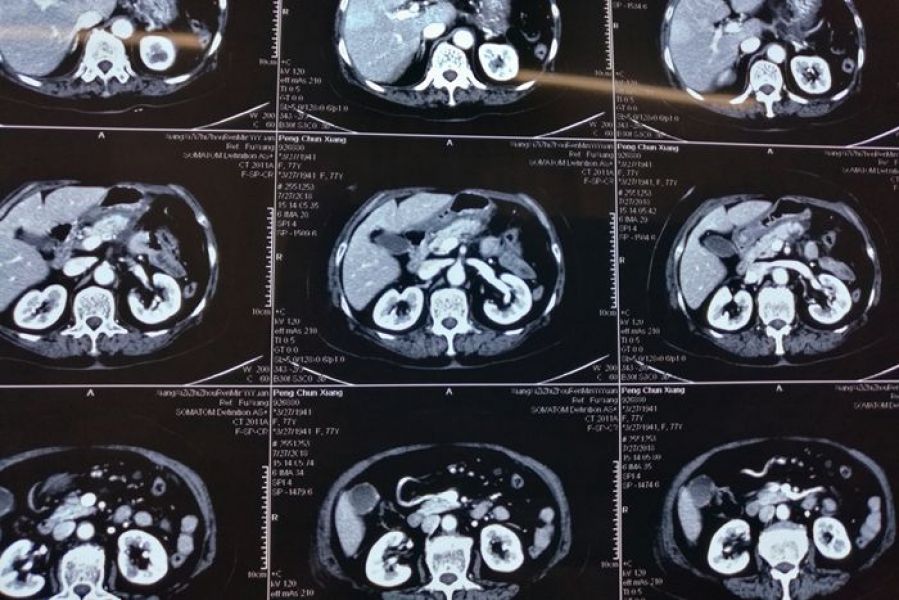

近日,肝胆外科成功为一名胰腺体尾部恶性肿瘤患者实施腹腔镜下根治手术。患者为七十多岁高龄女性,因左上腹部隐痛不适半月入住肝胆外科二病区,经CT及彩超检查显示,胰腺体尾部占位性病变。该科医生经过讨论分析,临床诊断为胰体尾部恶性肿瘤伴脾动脉侵犯,准备为其实施扩大的胰体尾癌根治切除术。

经过充分的术前准备,手术于7月18日进行,由肝胆外科主任宋新主任医师台下指导,肝胆外科二病区手术团队遵循目前最先进的根治性顺行模块化胰脾切除术(RAMPS)术式,从显露到配合,从分离到缝合,到计划性的en-block标本完整切除,都是按照术前精心设计的步骤顺利操作,历时5小时,出血不足50ml,最后成功为患者实施了3D腹腔镜下胰体尾癌联合脾脏切除术,切除7、8、9、10、11、12b淋巴结及左肾前筋膜。术后病理报告提示:胰腺体尾部低分化腺癌,肿瘤切除标本切缘阴性,淋巴结无转移。术后继续将加速康复理念应用于该患者,术后第一天拔出胃管,鼓励患者床上活动,肺功能锻炼;术后第二天拔出导尿管,开始下床活动。一周后复查胰腺CT提示病灶已完整切除,无出血及胰瘘等并发症发生,患者康复出院,目前回访无异常。

据肝胆外科医生介绍,胰腺癌被称为“沉默的杀手”,体尾部癌更少见,恶性程度更高,侵袭性强,易突破胰腺被膜,侵犯左肾上腺,甚至突破肾筋膜进入肾脂肪囊,而且在常规体检中,医生看不到或感觉不到这种肿瘤。为了帮助诊断,只能通过腹部的影像学检查(如超声或CT扫描)来发现。为做到淋巴结及周围脂肪组织的彻底清扫,近年来主张实施先进的胰体尾癌根治性顺行模块化胰脾切除术(RAMPS),绝大多数医院一直采用开放的手术方式。随着对上腹部解剖认知的不断深入,凭借丰富的开腹经验,加上历年来积累的熟练的腹腔镜操作技术,肝胆外科医生已成功完成多例腹腔镜下复杂的肝胆胰手术,借助3D腹腔镜,使得术野立体感更强,显露更清晰,使得医生更加有信心挑战更多复杂的病例。